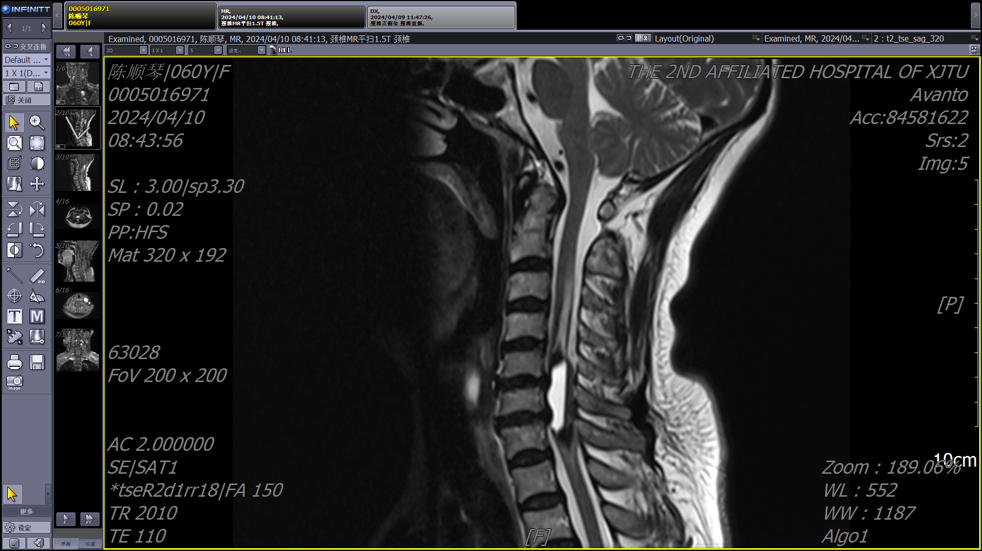

患者为一名中年女性,因颈部疼痛和四肢麻木症状就医,颈椎MRI检查结果显示颈4-7椎管内存在异常信号。由于病变位于颈段脊髓,手术风险极高,稍有不慎就可能导致瘫痪,多家医院的医生都遗憾地表示没有能力“接招”。